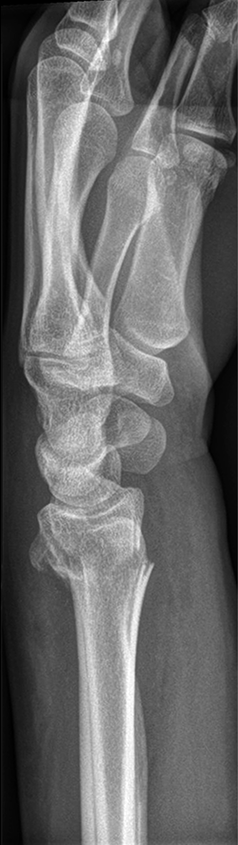

The patient was a 25-year-old woman who sustained a displaced, unstable extraarticular fracture of the left distal radius while snowboarding.

After closed reduction a dorsal re-dislocation of 25° occurred (Fig 4a). There are additional apparent signs of instability: dorsal comminution (Fig 4a) and fracture of the ulnar styloid (Fig 4b). Therefore, a considerable potential for further dislocation is present which is likely to occur in a cast. This young, active, and demanding patient wishes to return to her activities as early as possible. This can only be achieved with an operative fracture fixation. The nail was chosen instead of a plate. This allowed an almost instant functional use of her hand, which allowed her to return to work at 2 weeks postoperatively without additional fixation or a splint and full unprotected function of her wrist at 6 weeks.